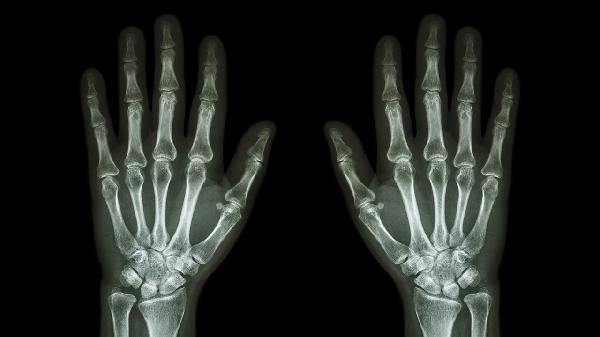

酒精在肝脏代谢为乙醛后会产生大量尿酸,当尿酸浓度超过血液溶解度时,会形成结晶沉积在关节腔。手指关节因末梢循环较差更易受累,表现为晨起关节僵硬、胀痛,活动后可能缓解。这种情况通常与饮酒量直接相关,减少酒精摄入后症状多可自行改善。

若患者本身存在高尿酸血症或痛风病史,酒精会抑制肾脏排泄尿酸,同时啤酒等酒类含有嘌呤会加剧尿酸生成。痛风发作时关节会出现明显红肿热痛,常见于第一跖趾关节,但手指关节也可能受累。此时需通过血尿酸检测确认,并可能需要使用非甾体抗炎药或降尿酸药物。

类风湿关节炎患者饮酒后可能因免疫紊乱加重晨僵症状。该病属于自身免疫性疾病,特征为对称性小关节肿痛,晨僵持续时间常超过1小时。饮酒会促进炎症因子释放,导致关节滑膜增生加剧。确诊需结合类风湿因子、抗CCP抗体等检查,治疗需规范使用抗风湿药物。